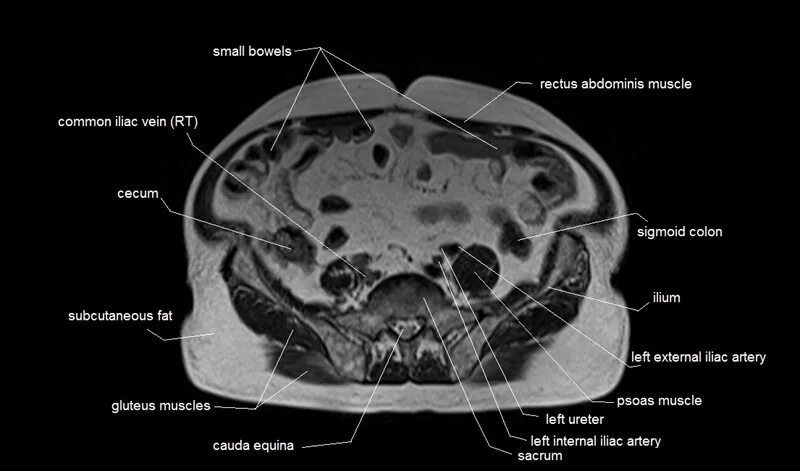

Labeled as